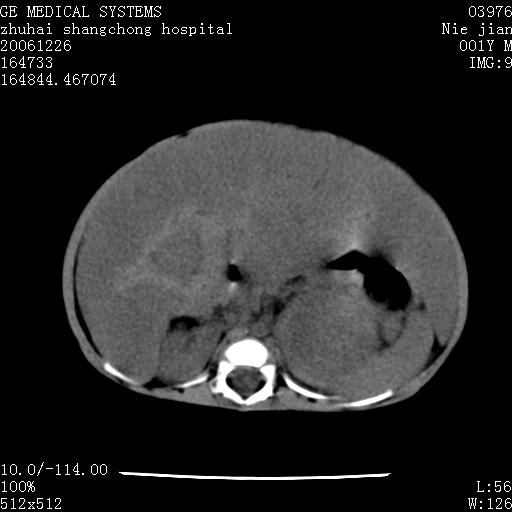

3个月婴儿腹胀来看。

【临床特点】

婴儿,腹胀,无特殊症状,未提供详细资料。

【影像特征】

1、肝明显增大,肝弥漫性低密度灶。

2、肾上腺区见类圆形肿块,其内密度不均,见片状偏高密度。

【诊断】

1、肝弥漫性病变,考虑急性肝炎致广泛脂肪浸润可能性大。

2、肾上腺区占位,假性肿瘤?肾上腺血肿(感染所致)?

一年后

1、肝硬化,脂肪浸润消失。

2、假性肿瘤消失或血肿吸收。

【分析】

1、关键着眼点:肝脏弥漫性病变内有没有走形的血管,仔细看部分低密度内有血管影(要有增强扫描作为证据就好了),说明并非肿瘤样病变,而是脂肪浸润。即可能不是转移瘤或原发肿瘤,低密度的形态上看,是片状,也不像肿瘤。

2、儿童肝炎最常见的是感染,有时食入性损害或药物也可致肝脏炎症,肝炎致大空泡型脂肪变性,是一种无痛性疾病,无症状,病因有营养异常、代谢性疾病、药物及病毒感染。所以脂肪变性与感染有关。

3、肝炎的结局是肝硬化,而恰恰一年后复查,已有肝硬化表现。肿瘤一般那会消失,那叫奇迹。

4、肾上腺出血也可见于败血症及感染,通常包块在数周内消失,ct表现包块内有偏高密度,可能是亚急性血肿的表现。假性肿瘤即腹部肠管积液、扩张血管及邻近结构的伪像。自然会消失。

5、因此,感染可以贯穿一切,解释一切。肿瘤自然消退?可能吗?那些应要无道理的创造奇迹的事情会那么容易发生吗?